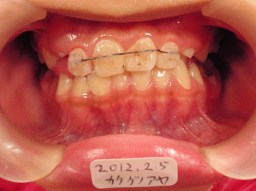

| 2012年02月05日(10才0ヶ月) 上記の約2ヵ月後 12番の反対咬合が改善 現在小臼歯や犬歯が生えるのを待っています。 |

|